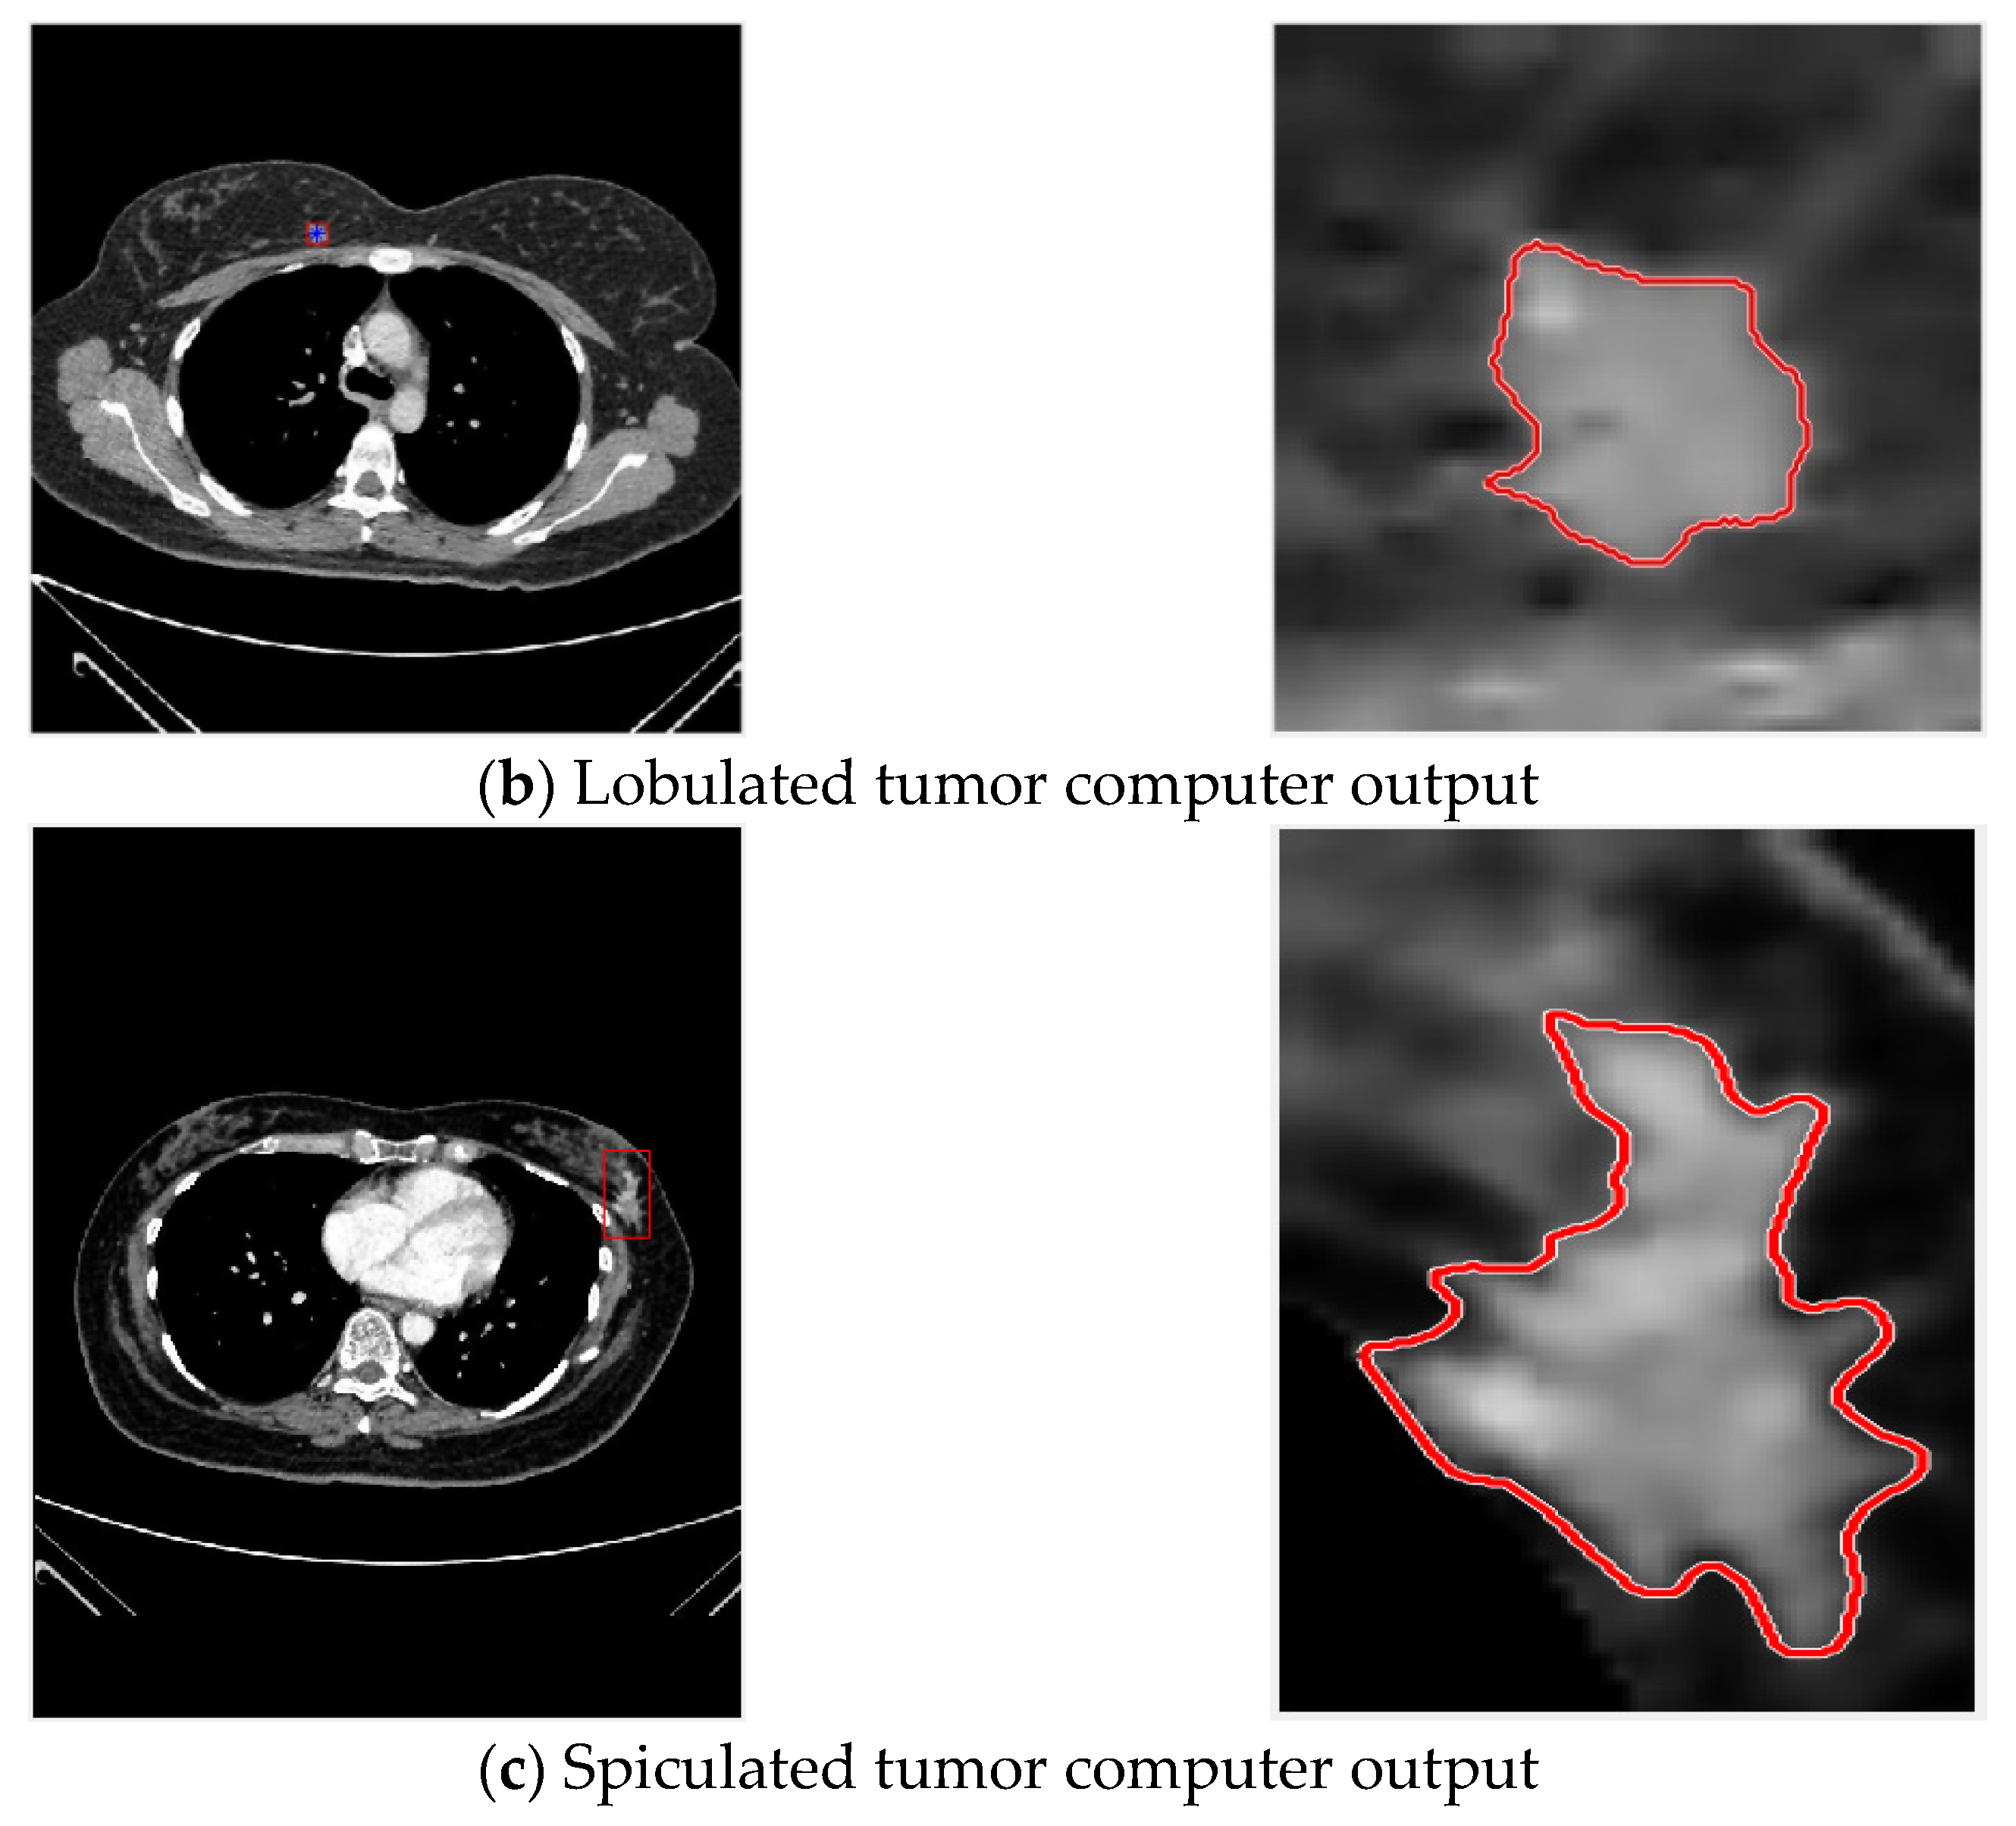

Then ACWE is used for tumor contour extraction, with circled results shown in Figure 7.

Figure 7.

Contour selection of tumors.

The result of convergence with the region-based active contour ACWE method is shown in Figure 8.

Figure 8.

ACWE contour circle selection results for spiculated tumor.